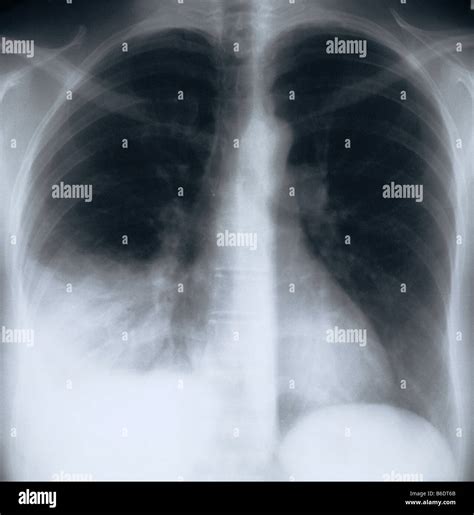

To a radiologist, a healthy lung appears mostly black on an X-ray because it is filled with air, which does not block X-ray beams. However, when pneumonia is present, the affected area of the lung becomes filled with inflammatory fluid and cells. This change in density causes the area to appear as white or grey patches, technically known as “opacities” or “infiltrates.”

• Patchy Infiltrates: Rather than one solid mass, the pneumonia may appear as scattered, cloudy spots throughout the lung tissue.

It is important to understand that not all cases of pneumonia are instantly visible. Several factors can influence how clearly pneumonia is depicted on an X-ray image:

Location Pneumonia located behind the heart or beneath the diaphragm can be difficult to detect.